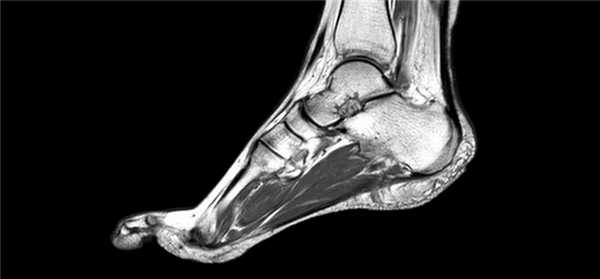

Стол заезжает в трубу - устройство, в котором создается сильное магнитное поле. Возбужденные атомы водорода в тканях и органах в ответ на воздействие магнитного поля испускают сигналы, которые и улавливает прибор. По ним компьютер воссоздает картину тканей в исследуемой области. Отдельные фото снимки объединяются в трехмерное изображение. Сустав можно исследовать в разных плоскостях.

Это и делает исследование таким ценным: как будто можно заглянуть внутрь голеностопного сустава и рассмотреть любое место с разных сторон с увеличением. Особенно ценная информация для хирургов: видны индивидуальные анатомические особенности строения сустава, места прохождения сосудов, нервов, их состояние. Врач планирует, исходя из полученной информации, оптимальный доступ к патологическому очагу, объем оперативного вмешательства, время, необходимое для выполнения манипуляций.

С помощью МРТ голеностопа врачи получают высококачественное изображение, при этом не нанося вред пациенту. На снимке можно увидеть:

- Суставной хрящ

- Костный мозг костей

- Суставы, связки, мышцы, сухожилия

- Сосуды, нервы

Для получения точной картины важно иметь возможность просканировать в трех взаимно перпендикулярных плоскостях. Также МРТ имеет высокое контрастное разрешение мягких тканей.